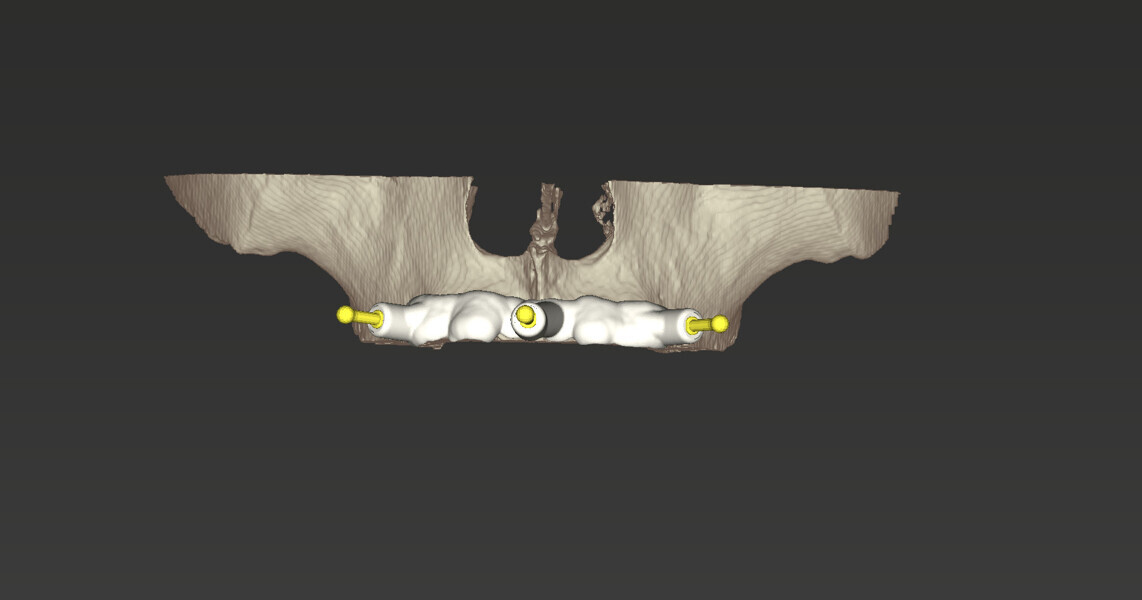

Compromised maxillary dentition treated with Straumann Pro Arch and a digital workflow